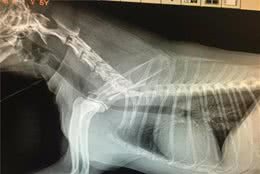

狗狗莫名其妙的尖叫是因为无聊?其实这尖叫是狗狗腰椎病疼痛引起

(一般宠物医院都是使用X光或者DR)狗狗得了腰椎病该如何治疗呢封闭治疗:这个是治疗腰椎病最常用的方法,治疗时间短、见效快、费用低还很安全,尤其是对于初次得腰椎病的年轻狗狗,有非常高的治愈率。方法:在狗狗腰椎增生的部位或骨刺的部位做封闭注射,...